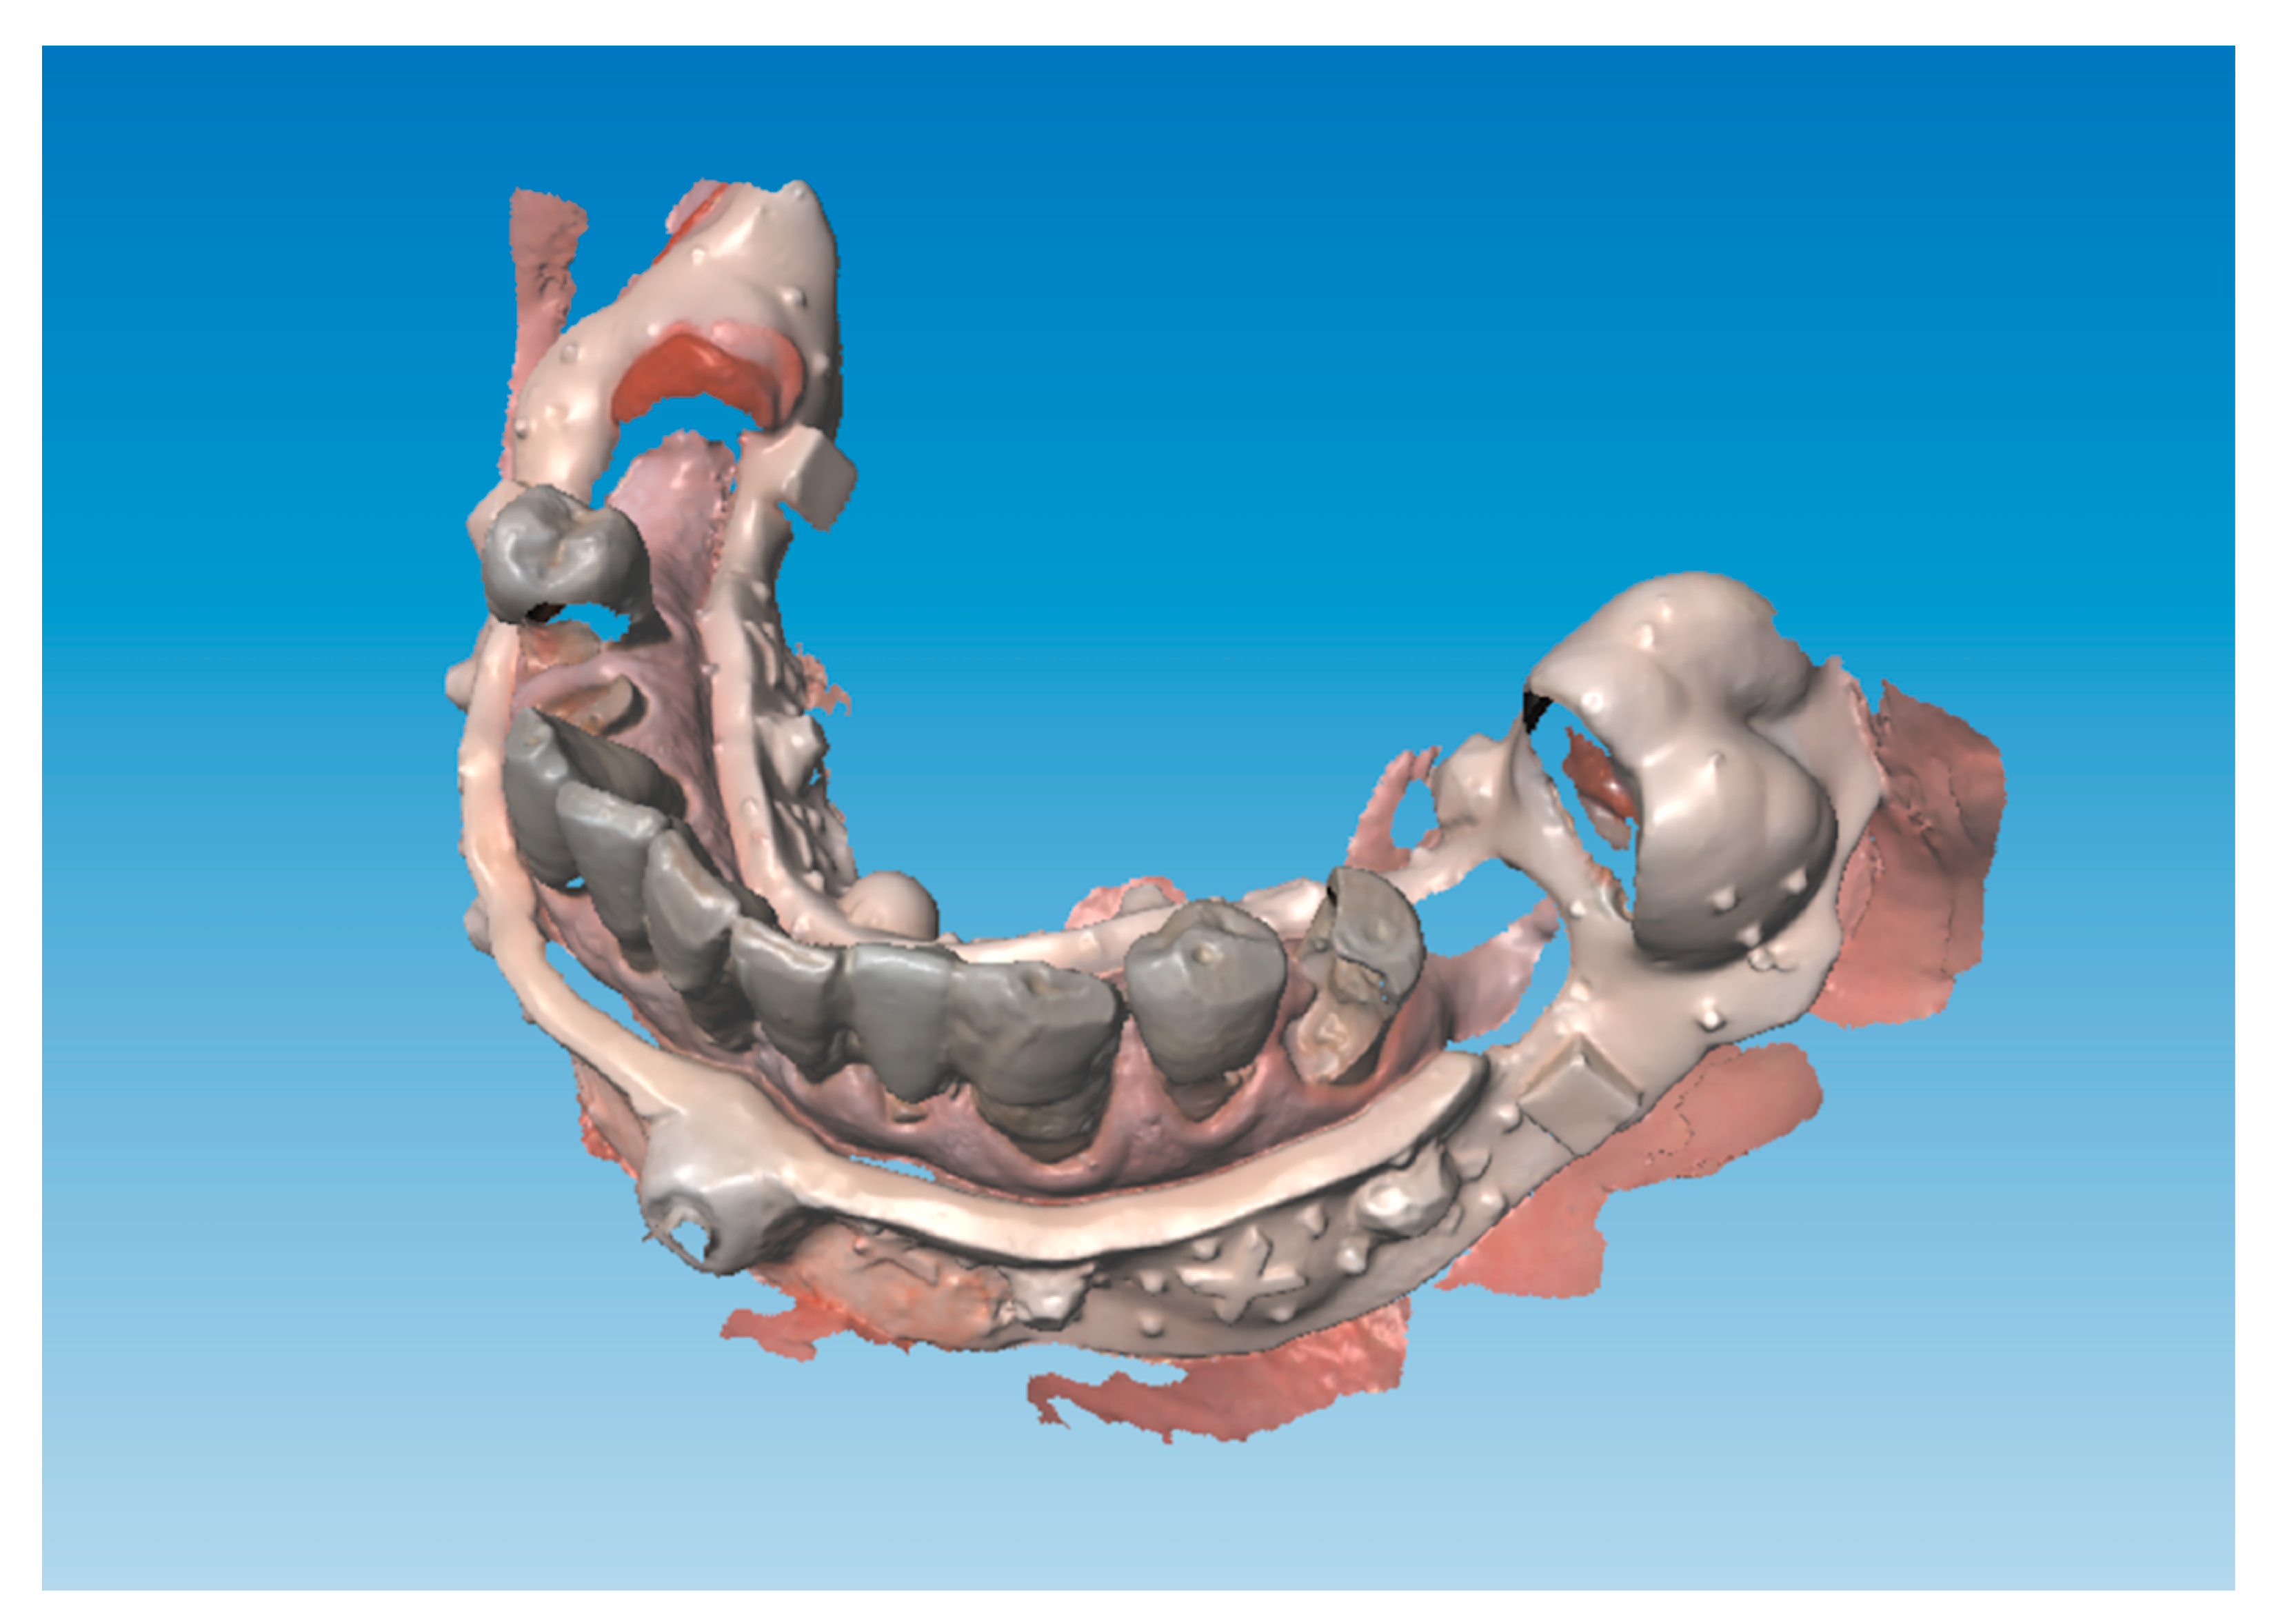

Extraction of all teeth was performed apart from the lower second molars that did not impair implant placement and served as distal support points for the digital index. Implants were inserted and scan abutments and the lower digital index was placed to take the postoperative digital impressions (Figure 7).

Postoperative impressions have been superimposed over preoperative records thus obtaining implant position and all the information about the three-dimensional relation between the maxilla and the mandible and ultimately the vertical dimension of occlusion (Figure 8).

Figure 7. Scan abutments and the lower digital index placement. (A) Scan abutment placement after implants insertion. (B) Placement of the digital index immediately after surgery to record the postoperative digital impression. (C) Postoperative digital impression in frontal view. (D) Occlusal view of the mandibular postoperative digital impression superimposed with the preoperative scan using the resin digital index as reference.